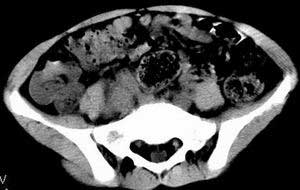

| 患者,男,9岁,因右下腹包块入院,血象不高,不规则发热,常超40度。 平扫: ![]() ![]() ![]() ![]() ![]() ![]() ![]() ![]() ![]() ![]() ![]() ![]() ![]() ![]() ![]() ![]() ![]() ![]() 增强: ![]() ![]() ![]() ![]() ![]() ![]() ![]() ![]() ![]() ![]() ![]() ![]() ![]() ![]() jiajie发言:骶椎右前区不规则软组织肿块,边缘光整,密度均匀,增强后均匀强化,右腹股沟区可见肿大淋巴结,临床有时发热,考虑淋巴瘤,儿童盆腔肿瘤应与神经母细胞瘤和横纹肌肉瘤鉴别。 longzhanghui发言:印象:盆腔右后壁不规则软组织肿块,并向前延伸.似为多个肿块融合,呈中等强化.初步考虑淋巴瘤. 听蝉观竹发言:右侧髂内、外组淋巴结肿大,从其形态和融合的情况看,同意大家意见-----考虑恶性病变,但是9岁男孩还要注意检查睾丸情况,有无隐睾? 常常类似情况是隐睾发生精原细胞瘤淋巴结转移,这个病例也要注意这一点!!! 广东凌发言:大家好,在这里我想说一下个人观点,我建议上传图片的同志能否辛苦一点就是把病史和图片都上传完整一点,比如这个病人的腹膜窗,并且这个病人的肠道的准备也是不怎么好,就从现有的质料看:病灶属于淋巴结肿大当无大的争议,有融合趋势,其内无坏死,边缘强化为主,故考虑:淋巴瘤!建议用腹膜窗看一下和肠道的关系! 阿圣发言:病灶属于淋巴结肿大当无大的争议,有融合趋势,其内无坏死,边缘强化为主,故考虑:淋巴瘤 结果是:淋巴瘤 病例来源:ct762。由宁静致远发布: http://www.radinet.com.cn/forum_view.asp?forum_id=4&view_id=2182 |